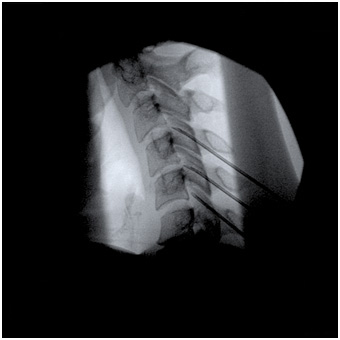

The doctor will then insert a thin needle directly into the

facet joint. Fluoroscopy, a type of x-ray, may be used to ensure the safe and proper position of the needle. A dye

may also be injected to make sure the needle is in the correct spot.

Once your physician is sure the needle is correctly placed, the medicine will be injected.